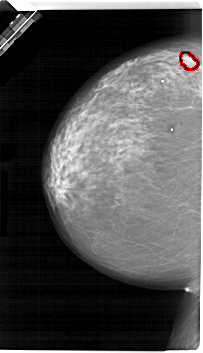

FILE: A_1657_1.LEFT_CC.OVERLAY

TOTAL_ABNORMALITIES 1

ABNORMALITY 1

LESION_TYPE MASS SHAPE LOBULATED MARGINS OBSCURED

ASSESSMENT 4

SUBTLETY 3

PATHOLOGY MALIGNANT

TOTAL_OUTLINES 1

BOUNDARY